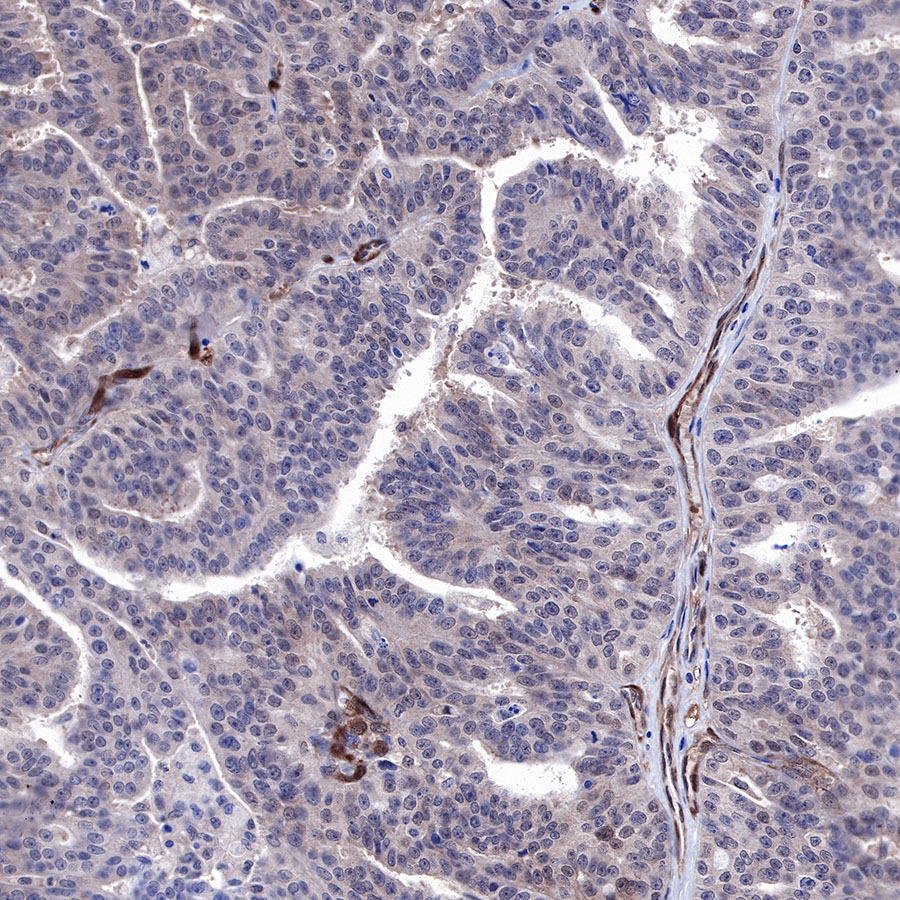

Immunohistochemistry

IHC shows positive staining in paraffin-embedded human ovarian carcinoma. Anti-PTEN antibody was used at 1/500 dilution, followed by a HRP Polymer for Mouse & Rabbit IgG (ready to use). Counterstained with hematoxylin. Heat mediated antigen retrieval with Tris/EDTA buffer pH9.0 was performed before commencing with IHC staining protocol.